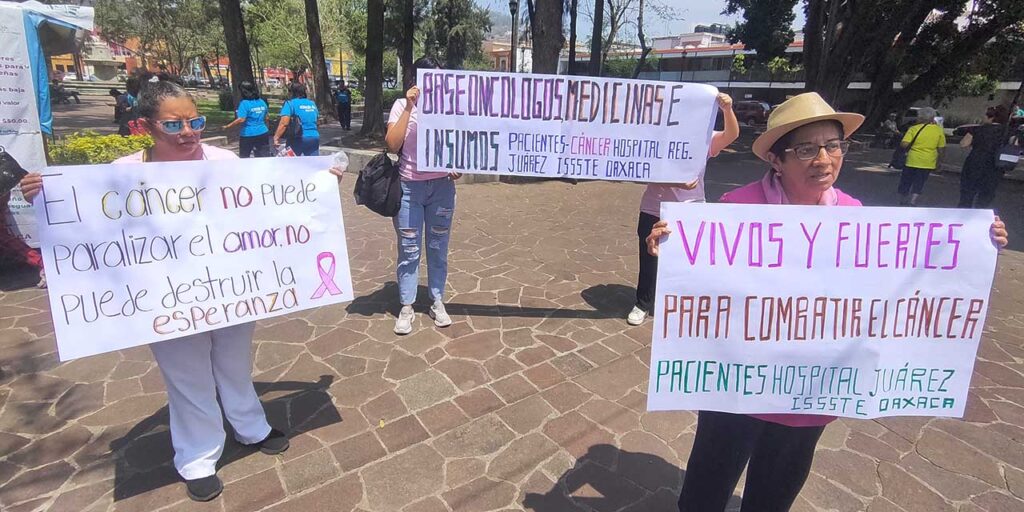

Pacientes con cáncer en Oaxaca recurren a medicamentos caducados ante desabasto hospitalario

Oaxaca, Oax., 23 de agosto de 2025. — La crisis del sistema de salud en Oaxaca ha llegado a un punto crítico: pacientes con cáncer en hospitales públicos de la entidad han recurrido al uso de medicamentos caducados para no interrumpir sus tratamientos, ante el persistente desabasto de fármacos oncológicos y complementarios. El drama de […]

Héctor, paciente oncológico firma alta voluntaria en hospital de Oaxaca ante desabasto de medicamentos

Héctor García Ríos denuncia abandono institucional en medio de su lucha contra el cáncer